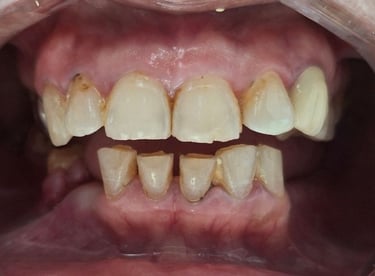

Before

After

All images shown here are real teeth cleaning cases treated at our clinic with patient consent.

Professional teeth cleaning helps remove plaque, tarter, and surface stains that regular at home brushing can not.

At Shree Dental Care, teeth cleaning is performed gently with focus on patient experience, comfort and long term oral health.